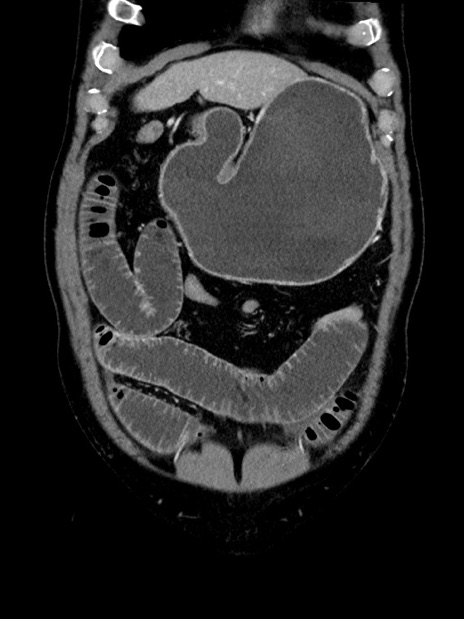

横断像

【症例】70歳代 男性

【主訴】腹部膨満、嘔吐

【現病歴】昨日より腹部膨満感出現。本日増悪し、仙痛出現。嘔吐あり、受診。

【既往歴】糖尿病、胆摘後

【身体所見】BP 149/80mmHg、HR 74/min、BT 35.9℃、腹部:膨満、軟、圧痛なし。腸雑音減弱あり。上腹部正中切開瘢痕あり。

【データ】WBC 13500、CRP 1.72